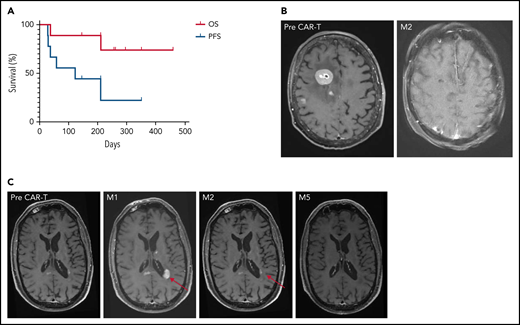

Survival and imaging of patients with R/R PCNSL treated with commercial anti-CD19 CAR T-cells. (A) OS and PFS. Median OS was not reached. Median PFS was 122 days for the whole cohort, increasing to 210 days for responders, vs 29 days for non-responders. (B) Patient 3: right frontal lesion at baseline and CR 2 months after CAR T-cell infusion. (C) Illustration of the flare effect suspected in patient 6: appearance of a left periventricular lesion 1 month after CAR T-cell infusion that dramatically decreased 2 and 5 months later. Despite high suspicion of a flare effect, response was reported as progressive disease according to the IPCG criteria, thus potentially underestimating PFS.

Between May 2020 and March 2021, 9 patients with R/R PCNSL were treated with anti-CD19 CAR T-cells: 7 received tisa-cel and 2 received axi-cel (Table 1). At time of infusion, the median age was 67 years old (range, 48-75 years) and median Eastern Cooperative Oncology Group (ECOG) scale of Performance Status was 1 (range, 0-4). Eight patients had brain parenchymal involvement, including 1 with intraocular localization, and 1 patient had an isolated cerebrospinal fluid (CSF) relapse. The median number of prior therapies before leukapheresis was 3 (range, 2-5), including ASCT in 7 patients. Bridging therapy was necessary in all but 1 patient because of the rapid evolution of R/R PCNSL and the time to manufacture CAR T-cells. At time of CAR T-cell infusion, following bridging treatment, 4 patients had progressive disease (PD) and 5 patients were in partial response (PR). One patient had ongoing corticosteroid treatment. The median follow-up after CAR T-cell infusion was 8.5 months. Seven patients experienced CRS (any grade), including 1 grade 3 after tisa-cel. ICANS of any grade occurred in 5 patients, including 1 grade 3 after tisa-cel and 1 grade 4 after axi-cel. Symptoms of ICANS included confusion, impaired handwriting, seizures, and status epilepticus. The median times from infusion to the onset of CRS and ICANS were 5 (range, 1-6) and 8 days (range, 5-21), respectively. The median times to resolution of CRS and ICANS were 3 (range, 2-9) and 4 days (range, 1-70), respectively. Four patients had grade 3 or higher cytopenia lasting more than 28 days. At 1 month (M1), OR was observed in 6 of 9 patients, including complete response (CR) in 3 of 9 patients. At M3, OR and CR were observed in 6 of 9 and 5 of 9 patients, respectively. Best response to CAR T-cells was PR in 1 of 9 (tisa-cel) and CR in 5 of 9 patients (2 axi-cel, 3 tisa-cel). Two patients died, 1 from PD and 1 from COVID-19 while still in CR. Median PFS was 122 days, increasing to 210 days for responders. Median DoR was not reached. Six-month OS, PFS, and DoR were 89%, 44%, and 67%, respectively (Figure 1A; supplemental Figure 1).

Patient 3 presented with high tumor burden and PD at time of CAR T-cell infusion, associated with an ocular infiltration. A remarkable response to CAR T-cells was observed, with a persistent CR on brain magnetic resonance imaging (MRI; Figure 1B). Because of a grade 4 ICANS with status epilepticus, an eye examination was not feasible. The level of interleukin-10 was measured at 1200 pg/mL in the anterior chamber at M6.16 A larger series is needed to evaluate CAR T-cell homing in the ocular compartment.

Patient 6 had an early brain MRI 9 days after CAR T-cell infusion because of clinical deterioration. New multiple contrast-enhanced nodular lesions of several millimeters were observed. On MRIs performed 7 and 19 days later, without any additional treatment, these lesions significantly decreased, but 2 new lesions appeared in the corpus callosum and left periventricular region (Figure 1C). These lesions then markedly decreased on subsequent MRIs at M2, M3, and M6. In parallel, clinical status dramatically improved, raising the potential of pseudoprogression linked to CAR T-cell therapy and the difficulty to assess the response.